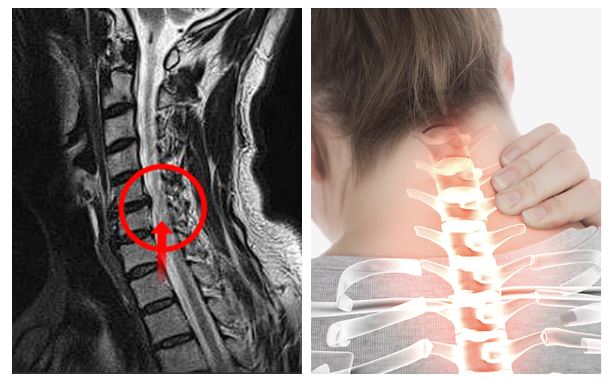

목 디스크는 목의 디스크(경추 디스크)에서 출현하는 질환으로, 경추 디스크 사이의 연골판이 터져 디스크 내부 물질이 경추 신경을 자극해 통증이나 저림증 등의 증상을 유발 해요. 목 디스크는 일상생활에서의 안 좋은 자세나 많은 운동, 부상 등이 이유가 되는 것이 될 수 있기도하고, 시간이 지날수록 발생 확률이 높아져요. 목 디스크의 증상으로는 목 부위의 통증, 팔의 저림, 근육 약화 등이 있으며, 증상이 난폭한 경우 수술 등의 치료가 필요할 수 있어요. 그리하나 대개의 경우 치료 없이도 시간이 지나면 증상이 호전되는 경우가 대부분입니다.

척수라는 중추 신경은 목뼈를 통과해 목 아래 감각과 운동 신경에 영향을 끼치기 때문에 목 디스크 증상들이 나타나면 신속하고 빠른 대처가 필요해요. 목디스크 치료형식으로 주로 초기 스탭에는 물리치료나 약물을 통해 대개의 환자들이 호전돼요. 그렇지 않다고 하면 신경 성형술과 차단술이라고 부르는 뼈주사 목디스크 치료방법을 이용하는데, 이 치료방법은 통증이 있는 신경 부위에 약물을 삽입하는 것입니다.

시술로써 눈에 띄게 질환을 현저히 치료하시는 것이 아니라 염증을 보완하고 통증을 낮추는 것이 포인트입니다. 이러한 방식으로 비 수술적인 치료를 3개월 이상 넘었음에도 불구하며 증상이 호전을 보이지 않으신다면 목디스크 치료방법 중 수술적 치료를 고심해야 하더라고요. 인공디스크를 투입하기 위함으로 절개를 통하기에 디스크를 제거하며 뼈를 하나로 유합 시켜서하는 것과, 내시경 수술로 빠져 나온 수핵 자체만을 제거시켜서하는 방법이 있다고하고요.

수술 방법에도 많은가 있다고 하는데 개괄적으로 설명을 하면 목을 절개해 망가진 디스크를 제거한 뒤 뼈를 하나로 유합하는 방법, 인공 디스크 투입술, 내시경을 활용해 바깥으로 빠져나온 수핵을 없애는 수술법 등이 있다고 합니다.